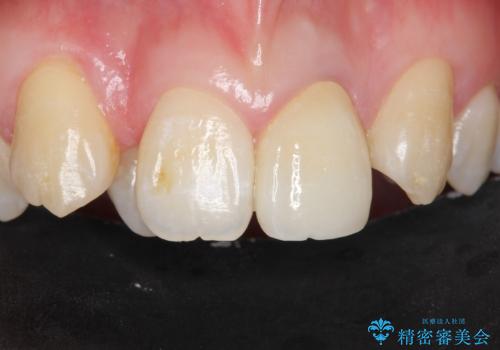

前歯の見た目を改善したい

[前歯の変色] 前歯の見た目を改善したい